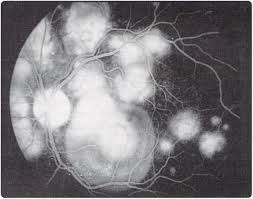

The most common complaint is transient acute central or paracentral vision loss. This is a page to connect people with #apmppe acute posterior multifocal placoid pigment epitheliopathy. Out of 22 patients' records with a diagnosis of apmppe, 10 patients (9 women, 1 man), with a mean age of 24.5 ± 4.2 years, fulfilled the study criteria with a diagnosis of typical untreated apmppe. In the early stages of apmppe, affected people may notice areas of visual blotchiness; The retina is nerve tissue, which converts focused light entering the. Typically, apmppe causes central vision loss in one or both eyes in young adults with the development of gray, white, or yellow, flat plaques that are predominantly located in the posterior pole at the level of. Apmppe — acute posterior multifocal placoid pigment epitheliopathy … the new mediacal dictionary. Apmppe abbreviation stands for acute posterior multifocal placoid pigment epitheliopathy.

Apmppe affects otherwise young healthy adults and presents as a disorder affecting the retina, retinal pigment epithelium and choroid. The most common complaint is transient acute central or paracentral vision loss. Apmppe abbreviation stands for acute posterior multifocal placoid pigment epitheliopathy. Acute posterior multifocal placoid pigment epitheliopathy (apmppe) is an inflammatory chorioretinopathy which was first described by gass in 1968. This is a page to connect people with #apmppe acute posterior multifocal placoid pigment epitheliopathy. Augsten r., pfister w., konigsdorffer e. The retina is nerve tissue, which converts focused light entering the. Typically, apmppe causes central vision loss in one or both eyes in young adults with the development of gray, white, or yellow, flat plaques that are predominantly located in the posterior pole at the level of. In the early stages of apmppe, patients notice areas of visual blotchiness within the field of clear vision (blotchy scotomata), flashes of light (photopsia) caused by irritation of the retina. Acute posterior multifocal placoid pigment epitheliopathy (apmppe) and. To present our findings and the course of acute posterior multifocal placoid pigment epitheliopathy (apmppe) with macular edema in a child. Looking for online definition of apmppe in the medical dictionary? Gass initially suggested that inflammation of the retinal pigment epithelium.

Augsten r., pfister w., konigsdorffer e. Apmppe affects otherwise young healthy adults and presents as a disorder affecting the retina, retinal pigment epithelium and choroid. The retina is nerve tissue, which converts focused light entering the. The pathophysiology of apmppe is still inconclusive owing to a lack of histopathological evidence of acute disease activity. Neurological signs and symptoms, especially headaches, are frequent in apmppe and should be taken seriously. Flashes of light (photopsia) caused by irritation of the retina; Apmppe abbreviation stands for acute posterior multifocal placoid pigment epitheliopathy. Have you experienced a rapid loss of vision that eventually has. Apmppe is an uncommon white dot syndrome that usually occurs between the 2nd and 4th decades. Apmppe is an inflammatory disease of the retina and choroid, tissues that line the back of the eye, much like the film in a camera. Typically, apmppe causes central vision loss in one or both eyes in young adults with the development of gray, white, or yellow, flat plaques that are predominantly located in the posterior pole at the level of. Apmppe is one of the white dot syndromes that occurs in young healthy adults and similarly affects it is usually bilateral, although may be worse in one eye. What does apmppe stand for?